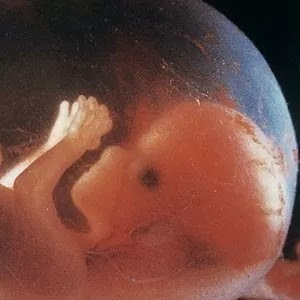

Desenvolvimento dos embriões humanos

O processo de desenvolvimento de um embrião humano ocorre em diversas etapas: fecundação, segmentação , gastrulação e organogênese .

Por fim, a organogênese , última fase do embrião. Ocorre a diferenciação dos órgãos e tecidos e o tubo neural é formado (neurulação) e o embrião é chamado de nêurula. Esse processo ocorre até a oitava semana de gestação (56º dia). A partir da nona semana, o indivíduo em desenvolvimento passa a ser chamado de feto e nasce, em média, a partir da 38ª semana de gestação.